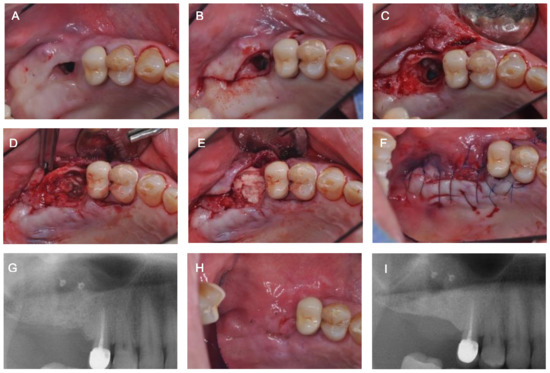

Implant Placement after Closure of Oroantral Communication by Sinus Bone Graft Using a Collagen Barrier Membrane in the Shape of a Pouch: A Case Report and Review of the Literature

2. Case Description